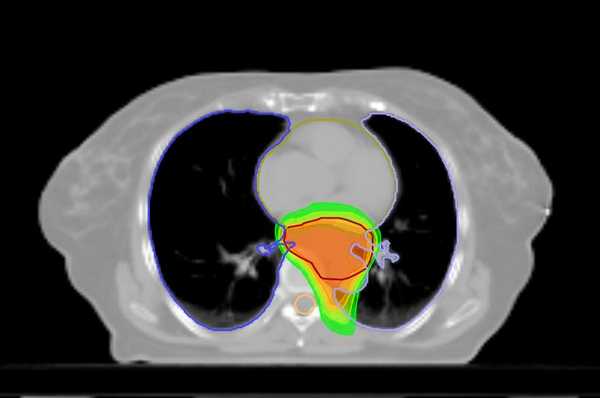

Принципиально иной подход предполагает применение инновационного метода лечения на аппарате Tomotherapy. Это устройство представляет собой облучатель, совмещенный с томографом, что позволяет максимально точно контурировать опухоль и не облучать окружающие ткани. Длительность лечения на аппарате составляет до полутора месяцев, а суммарно подводимая доза радиации — 40-50 Грей.